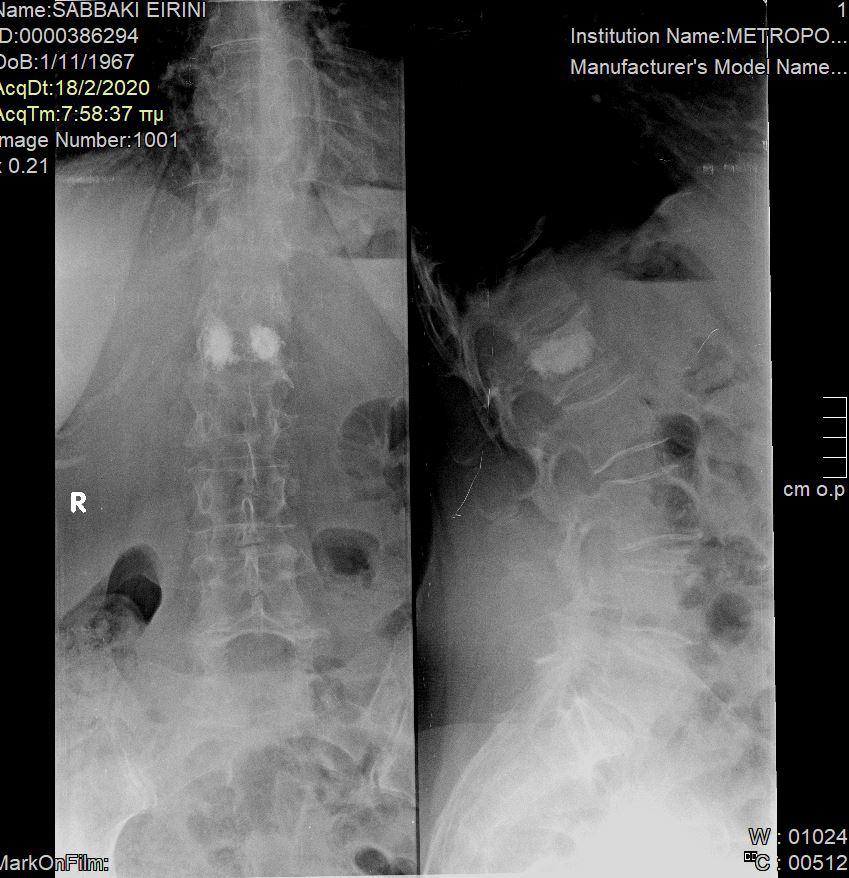

Με τη σπονδυλοπλαστική, εγχύεται ένα μίγμα οστικού «τσιμέντου» στον σπόνδυλο, προκειμένω να τον ισχυροποιήσει. Η διαφορά με την κυφοπλαστική είναι ότι στην κυφοπλαστική χρησιμοποιείται πρίν την έγχυση του τσιμέντου ένα μπαλόνι, το οποίο φουσκώνει μέσα στον σπόνδυλο, προκειμένω να αποκατασταθεί το ύψος και το σχήμα του σπονδύλου (Εικόνα 1 και 2).